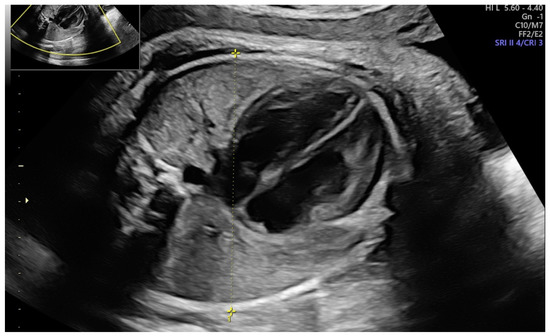

Accuracy of Fetal Biacromial Diameter and Derived Ultrasonographic Parameters to Predict Shoulder Dystocia: A Prospective Observational Study

2. Materials and Methods